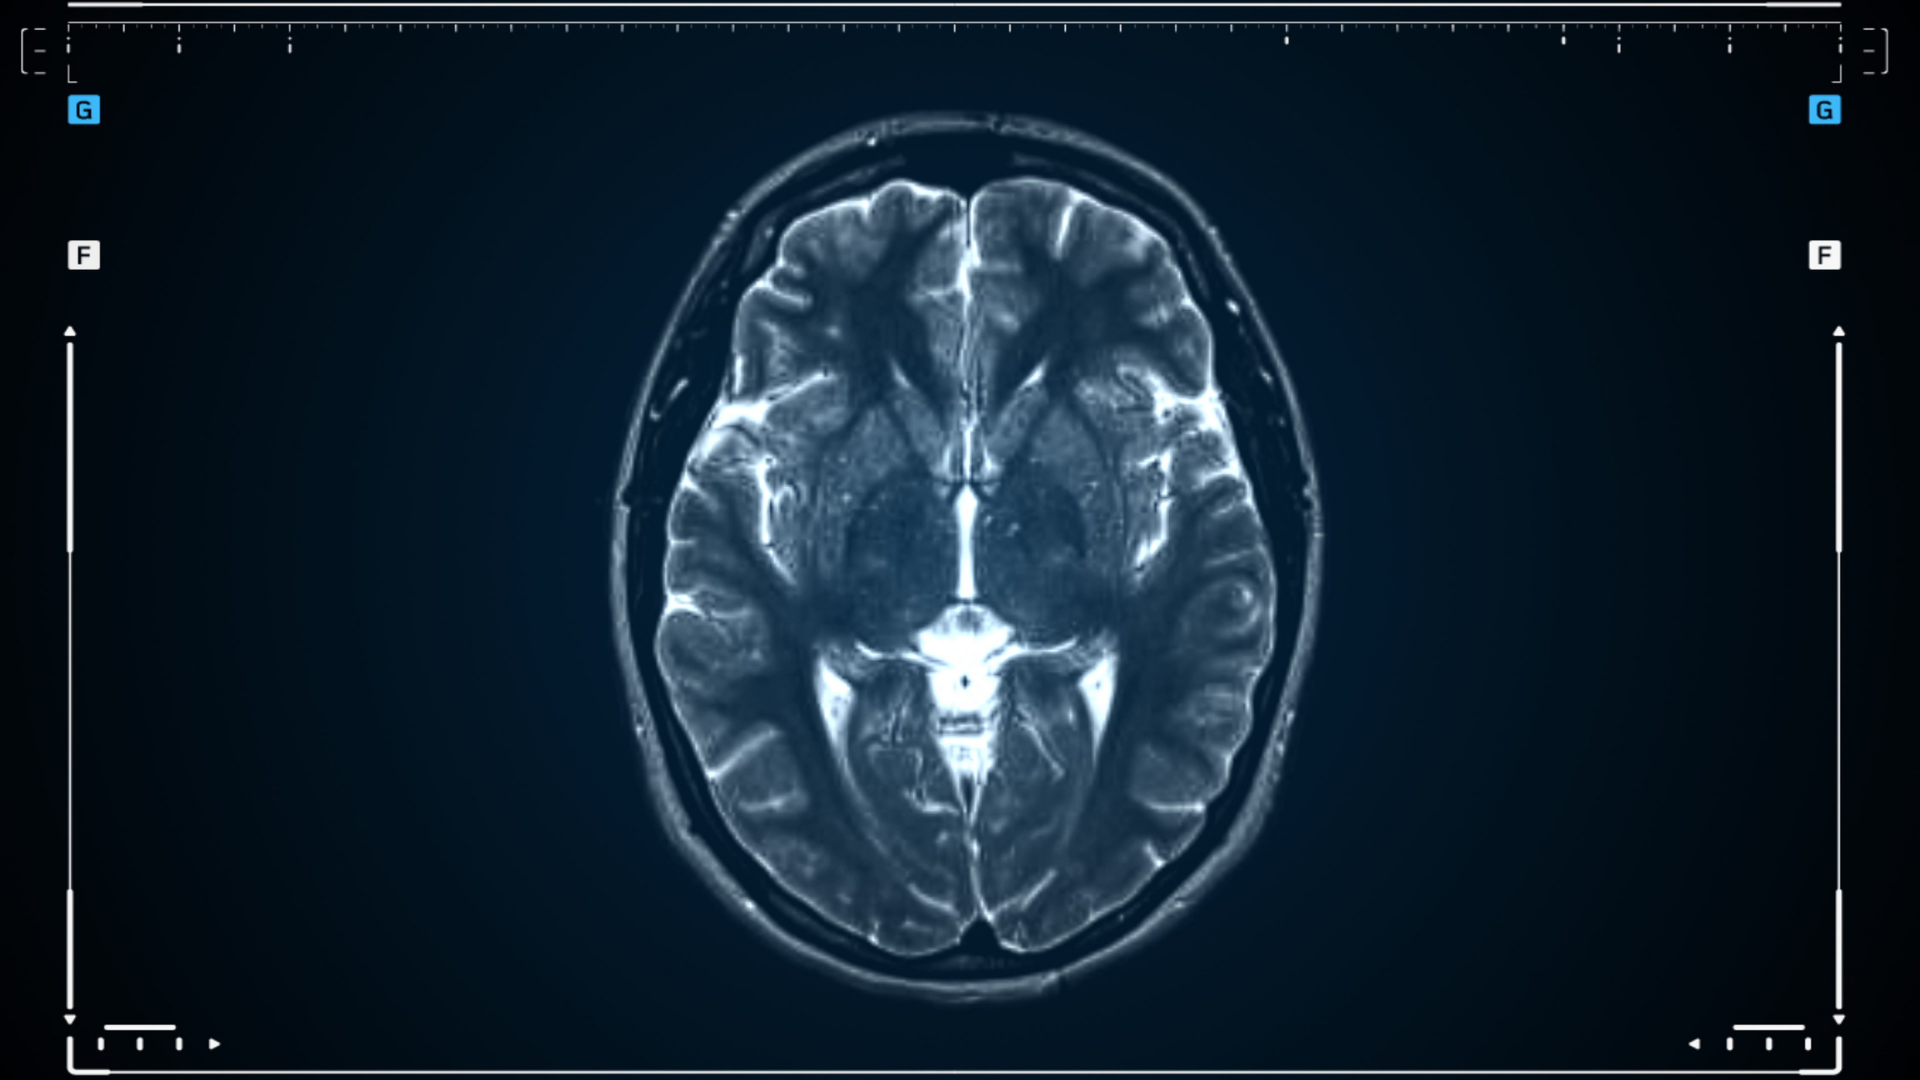

Chụp CT não là phương pháp chẩn đoán bằng hình ảnh sử dụng tia X và hệ thống máy tính để tạo ra những lát cắt chi tiết của hộp sọ và não bộ. Nhờ đó, bác sĩ có thể quan sát rõ cấu trúc xương hộp sọ và mô não. Trong trường hợp cần khảo sát mạch máu, có thể sử dụng biến thể như CT mạch (CTA) với thuốc cản quang. Phương pháp này còn được gọi là chụp CT sọ não hoặc chụp CT đầu để nhấn mạnh vị trí khảo sát.

So với các kỹ thuật khác, chụp CT não có tốc độ thực hiện nhanh và thường được chỉ định trong các tình huống cấp cứu. Việc chụp giúp đánh giá tổn thương kịp thời, từ đó đưa ra phương án xử trí phù hợp.